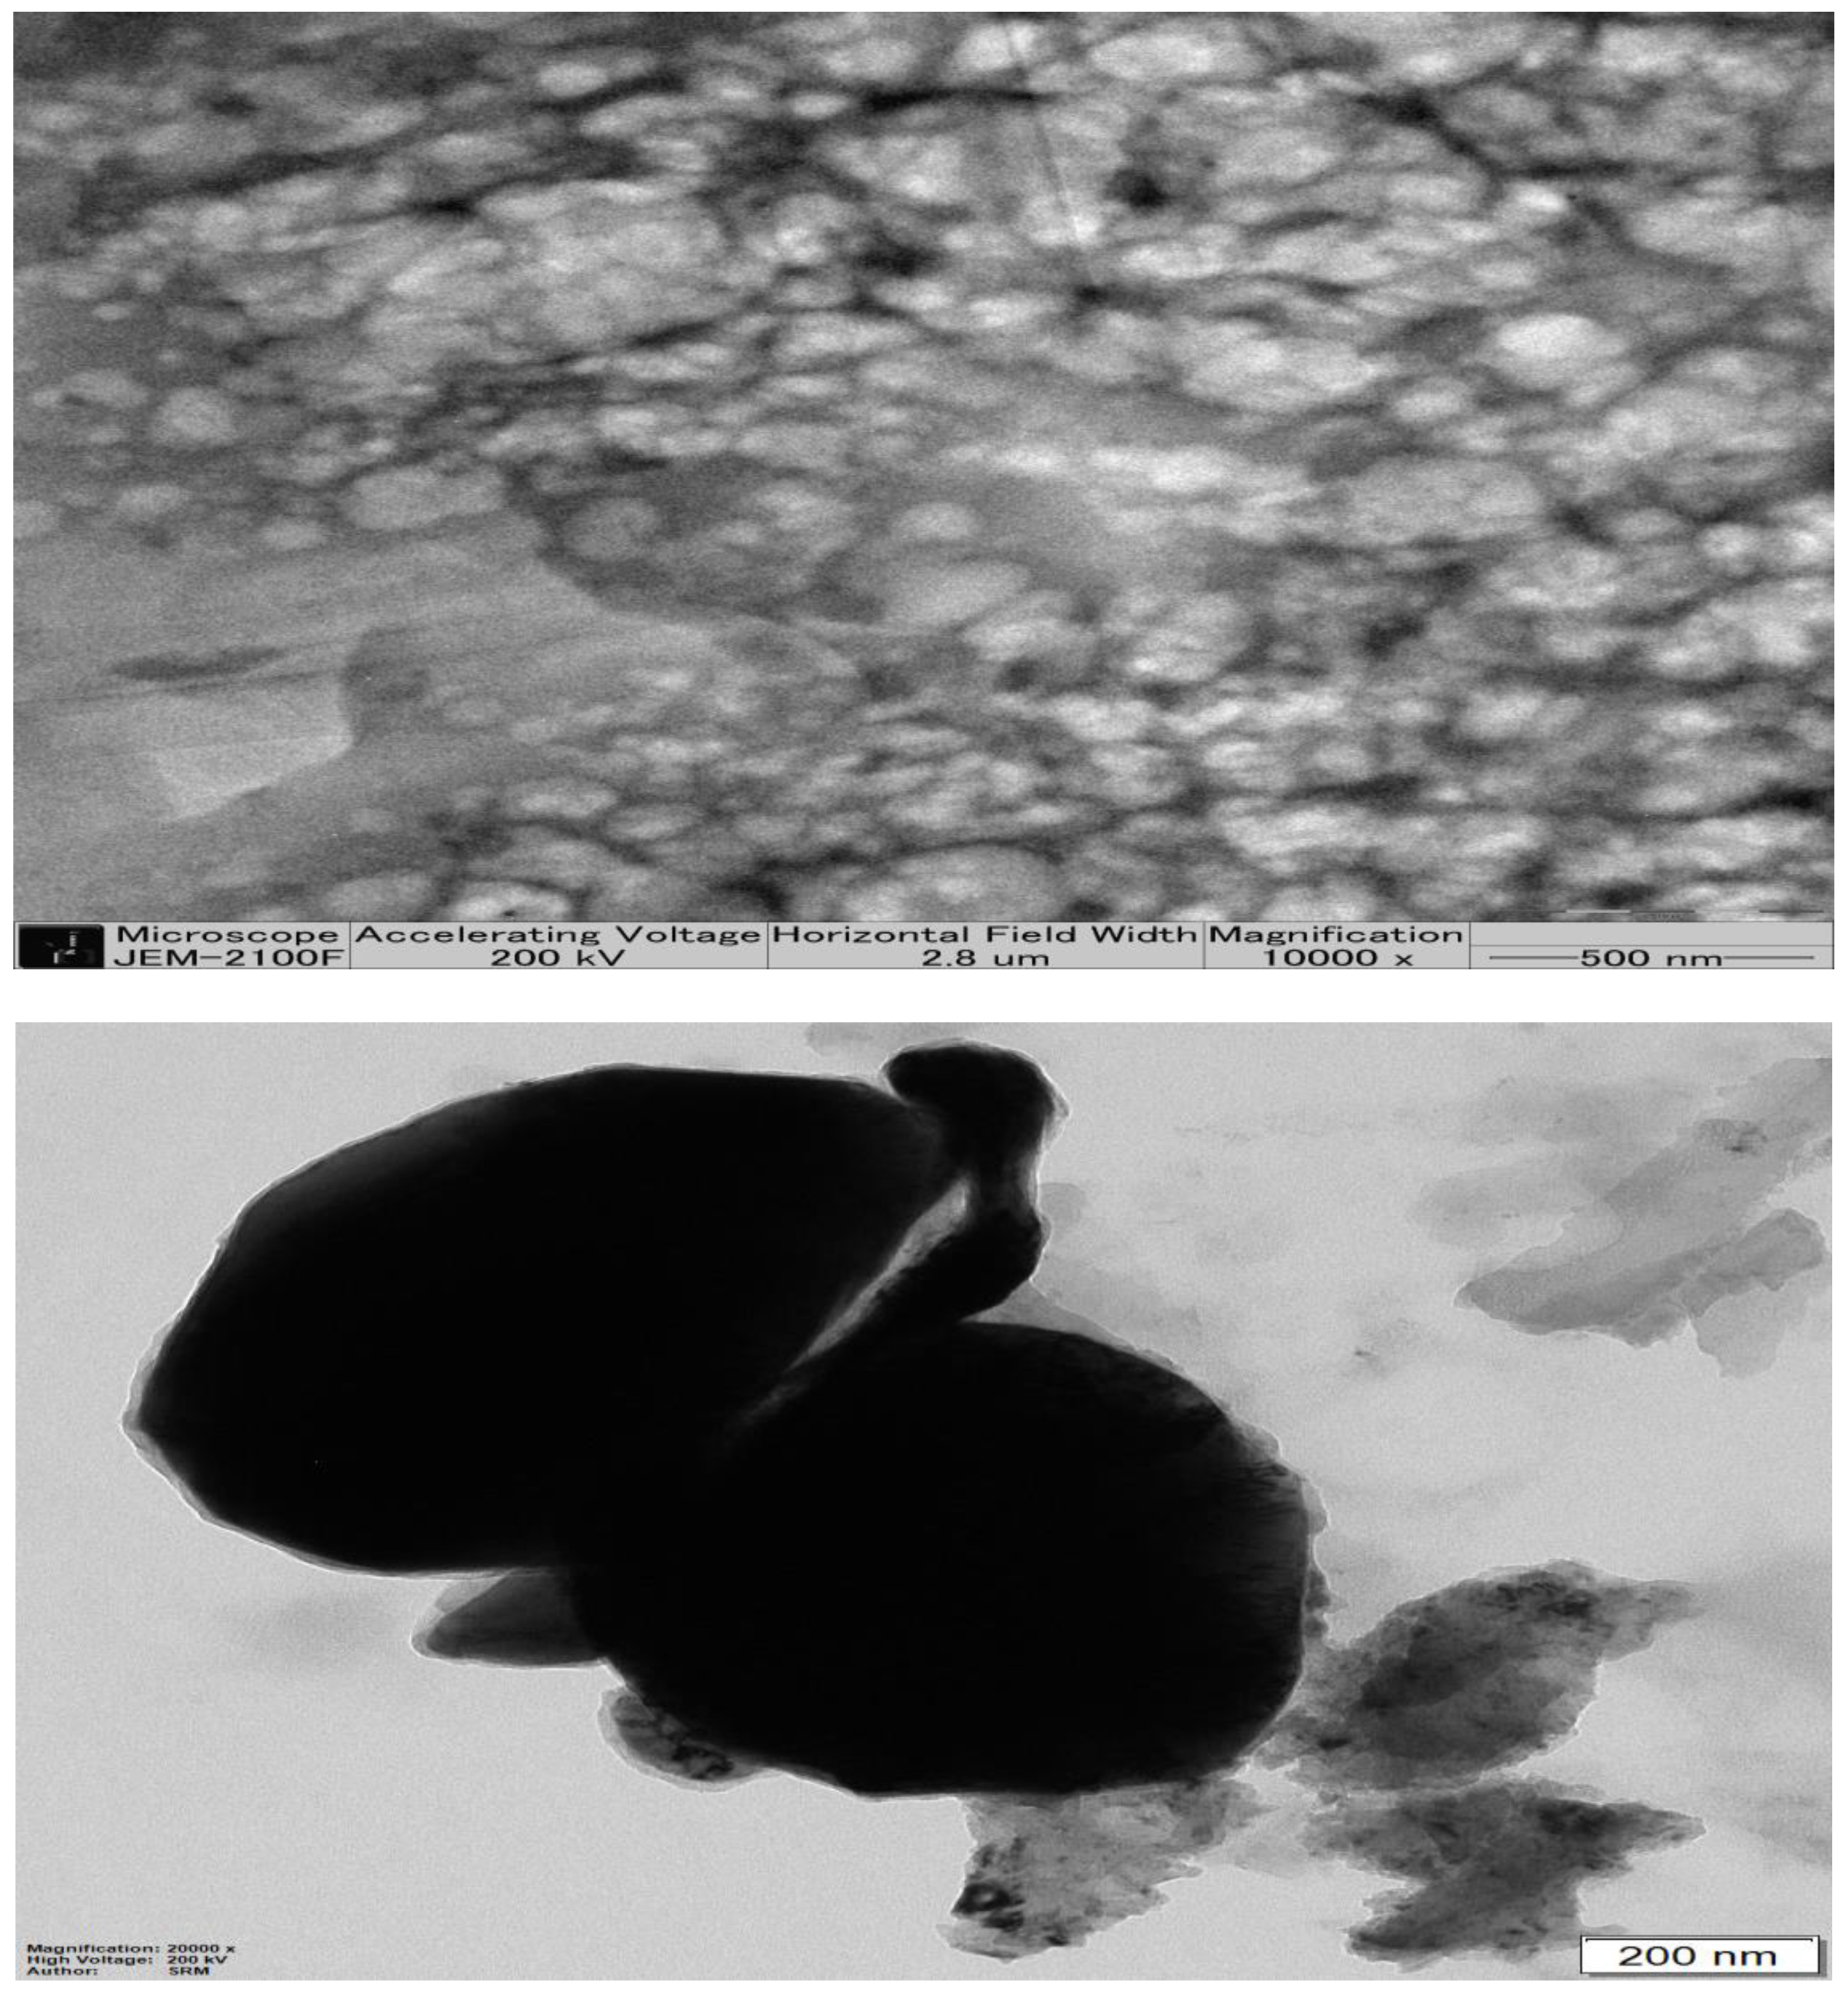

2.5. Transmission Electron Microscopy of Optimized β-ST-CUB

3.3.4. Transmission Electron Microscopy (TEM)